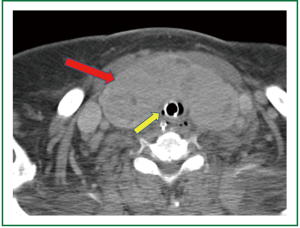

A 74 year old woman was referred for tracheostomy and open gastrostomy tube placement 17 days after suffering a hemorrhagic cerebrovascular accident secondary to a ruptured cerebral aneurysm. At baseline this patient’s Glasgow Coma Score was rated at 4 and the above procedure was scheduled in preparation for transfer to a skilled nursing facility. The patient’s medical history was significant for diastolic congestive heart failure, coronary artery disease, hypertension, aortic and tricuspid valve disease, mitral valve repair, morbid obesity, possible untreated chronic obstructive pulmonary disease, and a large thyroid mass. The thyroid mass was predominantly midline and completely covering the anterior and lateral surfaces of the trachea including the proposed surgical location for tracheostomy insertion (Figure 2). Therefore plans were made for a resection of the thyroid isthmus with central thyroidectomy for proper exposure prior to tracheostomy.

Supportive measures were immediately undertaken with multiple intravenous vasoactive medications, and blood pressure ultimately responded only to escalating doses of epinephrine and an epinephrine infusion. Given the above measurements and patient’s medical history, a cardiac event was considered most likely, but a jet ventilator associated complication could not be ruled out so no repeated attempts were made at jet ventilation. Due to the fact that the trachea was at this time fully exposed, the decision was made to insert the tracheostomy. Incision was made in the trachea and trachesotomy was inserted without incident. Upon arrival to the ICU, the patient continued to have hypotension. Decreased breath sounds were suspected on the left. A chest x-ray shot immediately after this finding confirmed large left-sided tension pneumothorax with mediastinal shift and evidence of left heart compression (Figure 3). A chest tube was introduced immediately relieving a large volume of air and allowing the weaning of the epinephrine infusion, with complete liberation of the infusion by post-operative day two. The patient was eventually deemed medically stable for transfer to a skilled nursing facility, after prolonged hospitalization, with a functional tracheostomy airway and nutrition with gastrostomy tube feeds.